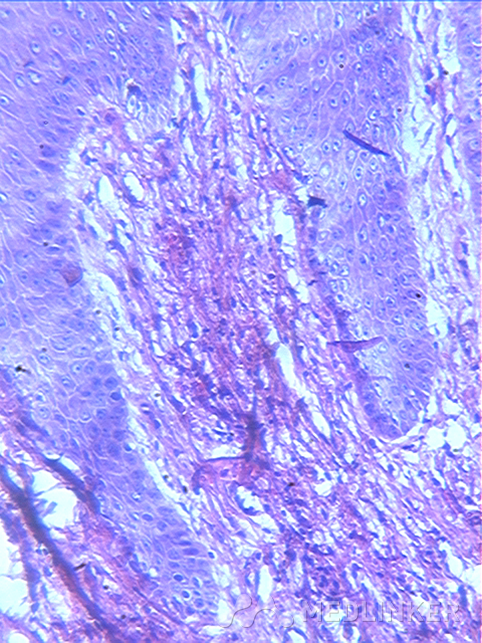

组织病理:角化过度,表皮增生,真皮乳头可见胶原增生与表皮排列垂直分布,真皮浅层血管周围少量炎细胞浸润。

讨论:获得性甲周纤维角化瘤临床表现,一般肿物长轴与侧甲沟走行一致,顶部角化,质硬,损害下甲板形成纵行凹陷.组织病理学活检提示:表皮角化过度,棘层肥厚,真皮可见大量增生的胶原纤维及成纤维细胞,增生胶原排列与表皮垂直分布。获得性甲周纤维角化瘤根据特征性临床表现及组织病理易被诊断,治疗以保留甲母质的外科手术切除为佳。需要与结节性硬化的甲周纤维瘤相区别。